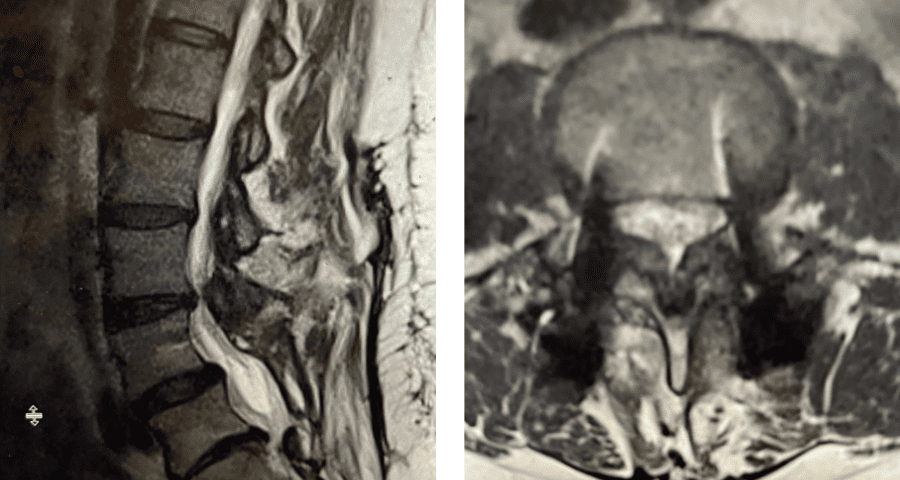

Figure 1. Sagittal and axial T2-weighted MRI of the spine demonstrating severe next segment stenosis above the prior fusion worse at L3-4 mainly due to severe ligamentous hypertrophy

This next patient was a 54-year-old female who had a long history of low back pain with radiation to both legs. She had a prior L4-S1 instrumented fusion and a L3-S1 laminectomy two years prior. In the past six months she has developed worsening low back pain and bilateral leg radiation. She had tried medications, epidurals, and PT but with no improvement. Imaging revealed severe stenosis above her prior fusion at L3-4 secondary to thickened ligament and facet hypertrophy or enlargement. This was also evident slightly less so at L2-3 (Fig 1). This ligament is in particular commonly involved in causing lumbar stenosis. This is a ligament that looks yellow in the operating room for which its purpose normally is to act like a rubber band to limit extremes of flexion and to aid in upright posture. Perhaps this ligament thickens to compensate for the decrease in upright support as we get older. It was decided initially to perform an L2-4 revision laminectomy, explore the prior fusion, and remove the hardware. We would leave the L4 screws in and add screws at L2 and L3, giving her a shorter segment of fusion mass if she was indeed fully fused.